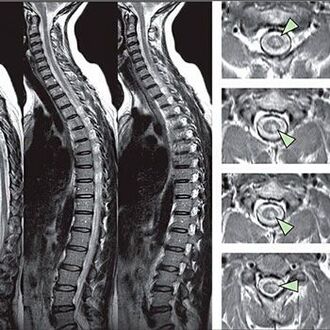

Aby sa identifikovali príznaky porúch citlivosti, vykonávajú sa špeciálne funkčné testy. Najinformatívnejšou možnosťou diagnostiky z inštrumentálnych metód je výkon X -Ray. Na dôkladnú štúdiu chrbtice sa však často vykonávajú MRI a CT. V prípade podozrenia na choroby kardiovaskulárneho systému sa pacient odporúča podstúpiť postup EKG.